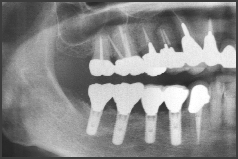

CASE1.60代女性

下の歯が欠損しており義歯をされていました。

治療前

治療後

綺麗な歯が入り、喜んで頂けました。

インプラントとアバットメント(土台)を入れました。

術後、綺麗な歯・歯ぐきになり、満足されました。